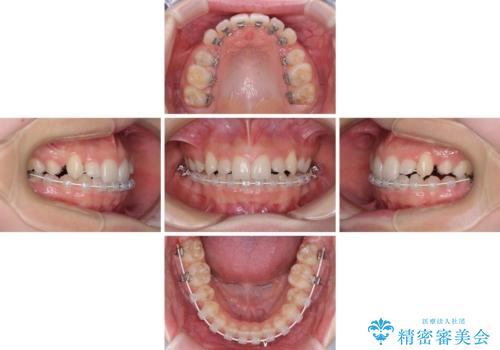

目立つ八重歯を目立たない装置で ハーフリンガルによる抜歯矯正

- 前歯のデコボコと八重歯を気にして来院された患者様です。

目立たない装置を希望されたので、上顎が裏側装置のハーフリンガルを選択し、左右上顎小臼歯1本ずつを抜歯して、矯正治療を行うこととしました。

治療期間の目安は2年半~3年間でしたが、予定通り治療が進み、2年半弱で終えることができました。

歯列はきれいに整い、治療期間も予定通りであり、患者様には大変満足していただきました。